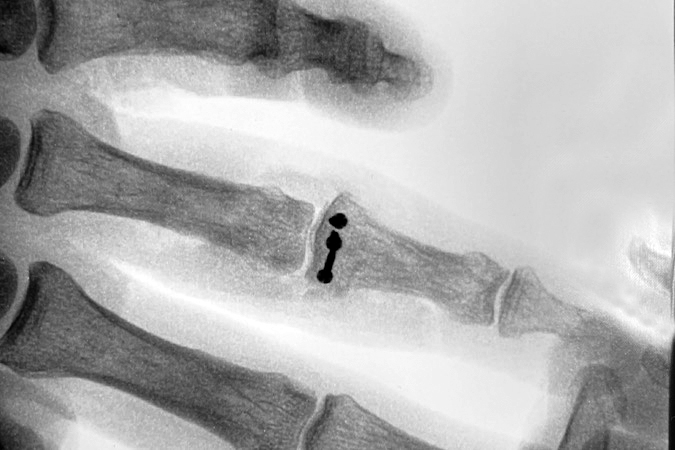

- if the injury leads to PIP joint instability, dorsal fracture-dislocations typically require surgery such as (ORIF) or hemihamate arthroplasty. The hemi-handmade arthroplasty is excellent option for treating unstable comminuted dorsal PIP joint fracture-dislocations. This procedure is usually indicated when 50% or more of the volar middle phalanx is fractured, thus producing an unstable dislocation. This procedure was first described by Hastings at the 1999 American Society for Surgery the Hand annual meeting. This procedure is done through a volar approach to the PIP joint. A “V” or zigzag incision is made in the skin, the flaps mobilized, the neurovascular structures identified and protected, and the flexor tendon sheath visualized. The A3 pulley is opened, if not already opened by the injury. The A2 and A4 pulleys are preserved. The flexor tendons are retracted exposing the volar plate and more distally the volar fracture in the middle phalanx. This is followed by releasing the attachments of the volar plate to the accessory collateral ligaments. This release allows the volar plate to be folded back proximally, thus exposing the rest of the middle phalanx fracture site. Fragments of bone and articular surface that are attached to the plate are removed. Next, the collateral ligaments are released, and the joint is hyperextended into the “shotgun” position. The defect in the volar middle phalanx’s articular surface is assessed. A rongeur or small saw is used to shape the defect so that it can accommodate a block-shaped osteochondral graft. The defect’s size is measured carefully. The joint is temporary reduced and attention turned to the donor site of the ipsilateral ring, little and hamate joint. After carefully locating the joint, a dorsal incision is made to expose the joint while simultaneously protecting the extensor tendon and the dorsal ulnar sensory nerve. At the ring, little, and hamate joint level the periosteal and capsular flaps are raised to allow visualization of the joint and the dorsal hamate. Next, a block-shaped graft centered on the apex of the hamate at the joint between the ring and little metacarpals is marked and carefully measured. The block graph should be slightly larger than the measured defect in the base of the middle phalanx. The longitudinal hamate cuts are made first. The proximal transfer osteotomy in the hamate is then performed. The final cut is made with the appropriately sized curved osteotome. Some surgeons start proximally through a notch in the proximal hamate, while other surgeons start distally with or without removing a portion of the ring and little metacarpal bases. Do not make the graph too thin, do not fragment the graft, and do not damage the articular surface of the hamate or the metacarpals. Once harvested, the block graft is brought to the finger and placed in the middle phalanx defect. It is temporarily held in place with a small K-wire. The surgeon should align the articular surface anatomically and tilt the graft to assure a cup -shaped surface of the middle phalanx base as visualized from the lateral aspect of the PIP joint. Note, the cartilage of the hamate is often thicker than the cartilage of the middle phalanx which may affect the appearance of the PIP joint on X-Ray. On occasion, adding extra cancellous bone graft from the hamate is needed distally in order to provide the proper tilt of the block-shaped graft and facilitating the curved laterally visualized cup shape of the base of the middle phalanx. Note, morphologic studies have shown this graft is not a perfect match to the volar middle phalanx base but typically variations have not affected the clinical outcome. Secure the graft with two or three 0.9 two 1.5 mm screws through the graft and into the dorsal middle phalanx dorsal cortex. Remove the K wire. Reduce the joint and reattach the volar plate to the stumps of the collateral ligaments left on the base of the middle phalanx. Check the range of motion and the stability. Close the wrist and finger incisions. Splint the PIP joint in 15 to 20 degrees of flexion. Start post-operative range of motion exercises at 7 to 10 days.23-27 For more information on hemihamate arthroplasty see the surgical images below and the links to HAND.E.

- ORIF with an autologous hemihamate osteoarticular graft may be required for PIP fracture-dislocations in which more than 50% of the base of the middle phalanx is fractured with an intact dorsal cortex.10

- The hemi-hamate autograft and screw fixation procedure has been associated with satisfactory results in 13 patients with PIP joint fracture-dislocations.10